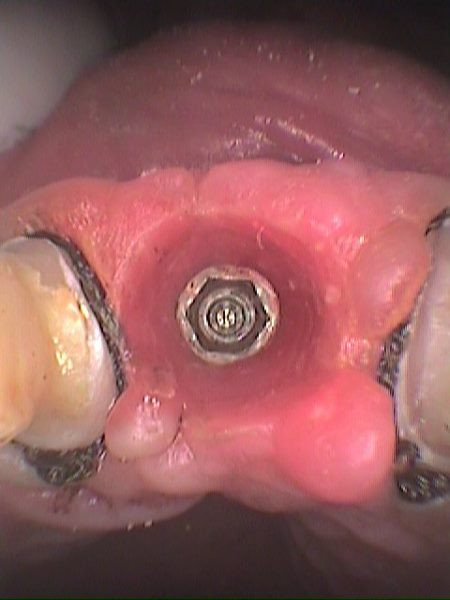

Se remueve tornillo de cicatrización

Vista clínica implante

Vista oclusal previa impresión